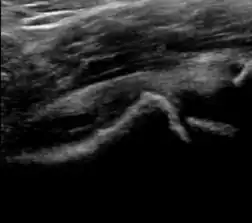

A step between the head and the physis can be detected in children with SCFE, while abnormalities in the femoral head contour may suggest the presence of LCPD. In both cases, radiographs are mandatory to confirm diagnosis and severity (Figure 12).[1]

Figure 12:

-

Normal ultrasound appearance of the femoral head-neck junction. -

Joint effusion in transient synovitis of the hip. -

Flattening of the femoral head in a patient with Perthes disease. -

Step in the femoral head-neck junction in a patient with SCFE.